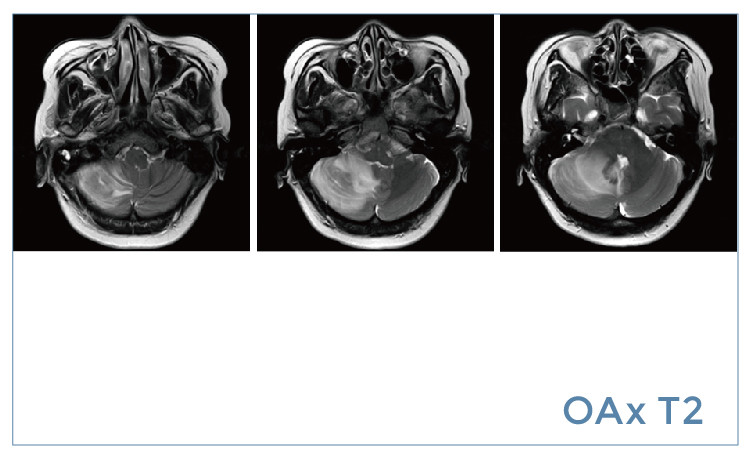

【朗润影像档案】20190726磁共振影像病例结果讨论

【朗润影像档案】磁共振影像病例分享(编号20190726)